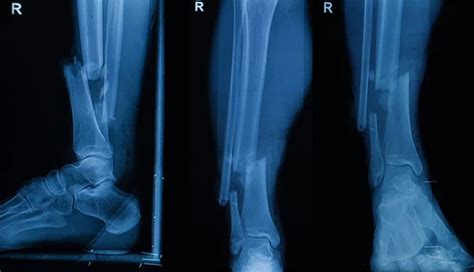

So, you’ve got a patient who’s just sustained a fracture. Your first priority, guys, is to conduct a thorough initial assessment . This isn’t just about looking at the obvious bump or deformity; it’s a comprehensive head-to-toe evaluation. You need to assess the mechanism of injury to understand how the fracture likely occurred, which can give you clues about the severity and potential associated injuries. Don’t forget to check for the ‘5 Ps’: Pain , Pallor , Paresthesia , Paralysis , and Pulselessness . These are critical indicators of potential neurovascular compromise. Pain management is paramount from the get-go. We’re talking about administering analgesics as prescribed, and sometimes even helping to decide the most appropriate pain relief based on the patient’s presentation and the type of fracture. It’s about alleviating suffering and also preventing complications like shock. We also need to assess the skin around the fracture site for any open wounds, which could indicate an open or compound fracture. Open fractures are a big deal, guys, because they carry a higher risk of infection. So, we need to cover any open wounds with a sterile dressing immediately. Immobilization is another key aspect of initial management. You want to stabilize the injured limb to prevent further damage to surrounding tissues, blood vessels, and nerves. This might involve splinting the area above and below the suspected fracture site. Remember, gentle handling is crucial. We don’t want to exacerbate the injury! Always compare the injured limb to the uninjured one to get a baseline for your assessments. And if you suspect a fracture, assume it is a fracture until proven otherwise by diagnostic imaging like X-rays. Your prompt and accurate initial assessment sets the stage for the entire treatment and recovery process, so it’s super vital that we get this right.